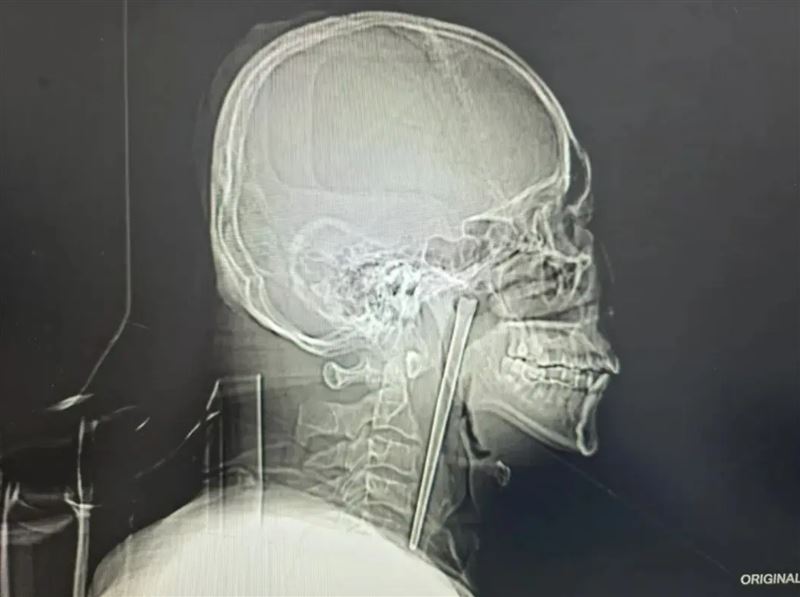

中國遼寧省大連市一名46歲王姓男子,近日因為咽部突然疼痛、有異物感就醫檢查,不料檢查結果嚇傻眾人,竟然在男子的喉嚨發現一根12公分長的「金屬筷子」,而這根筷子已經在男子的咽部藏了整整8年。

直到近日某天早上起床,王先生咽部明顯疼痛,即使休息情況也未緩解。立刻趕往醫院檢查,結果發現他的側咽壁上方軟顎後,金屬筷子已經嵌入其中,外露部分約3公分,不過並未出現明顯潰爛、出血、化膿等情況,聲帶正常、喉腔結構也沒受到壓迫移位。

最後醫院採用微創手術的方案,無需頸部開刀,最終將這根12公分長的不鏽鋼筷子完整取出,整個手術過程相當順利,未出現任何併發症,目前王先生已經順利康復出院。